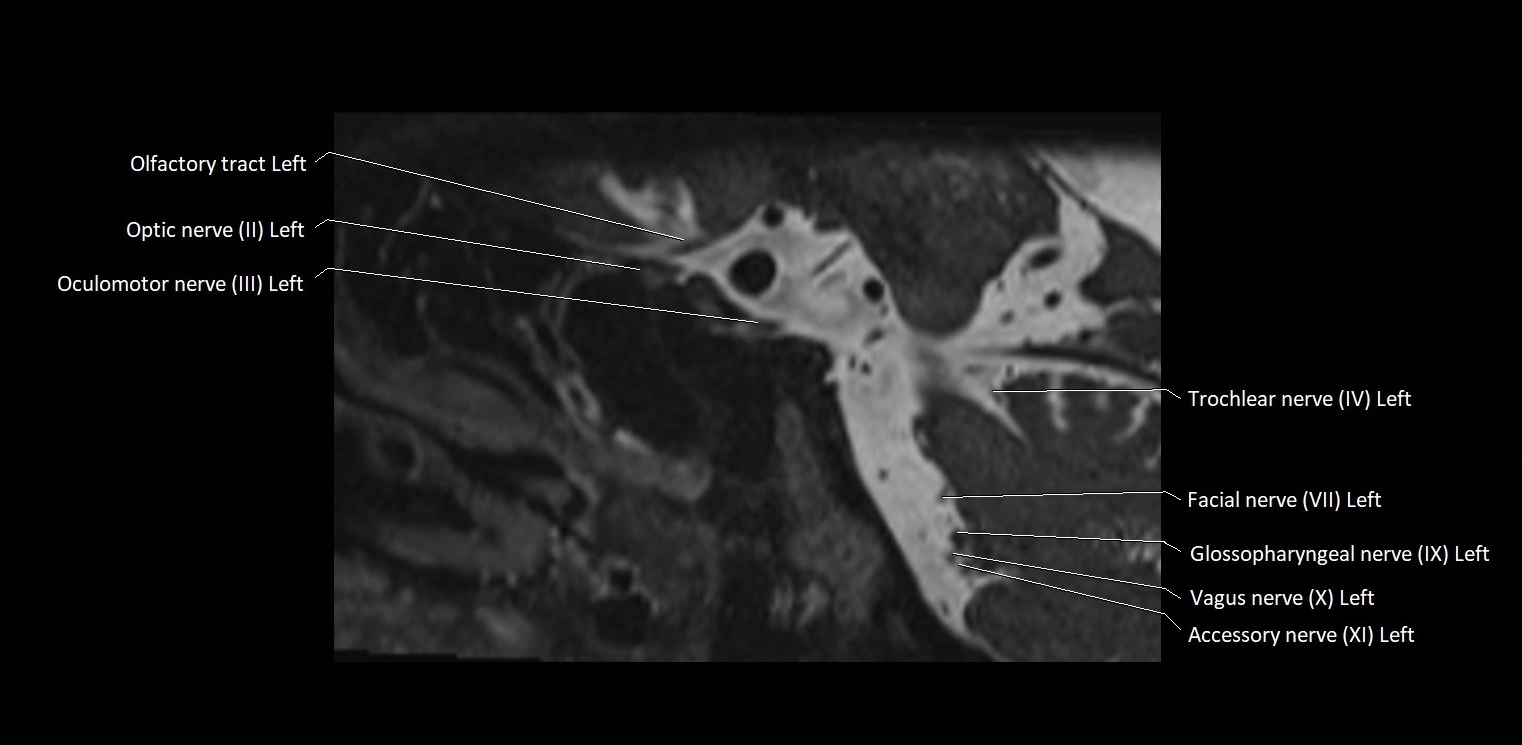

MRI Appearance

• The abducens nerve is a small, thin, linear structure

• Best visualized on high-resolution T2-weighted 3D MRI sequences (e.g., FIESTA or CISS)

• Seen as a hypointense (dark) line running from the brainstem at the pontomedullary junction, traversing the prepontine cistern, and entering Dorello’s canal under the petrosphenoidal ligament, then into the cavernous sinus, and finally the orbit

• May be challenging to visualize in standard MRI due to its small size

• Pathology may be inferred by absence, displacement, or enhancement of the nerve

MRI images

image